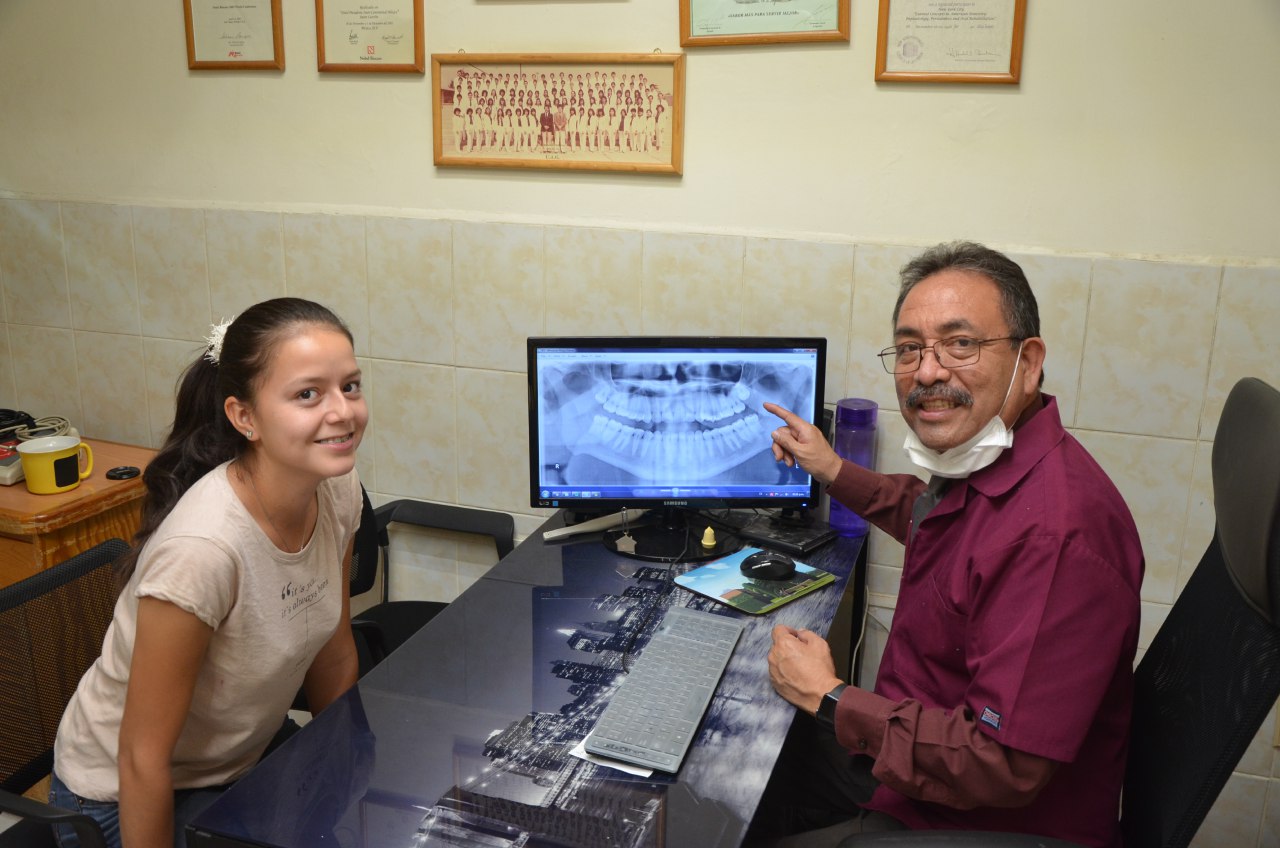

Rehabilitacion integral

La rehabilitacion integral usa distintos medios y tecnicas para que Usted recupere la funcionalidad de su dentadura al 100%.